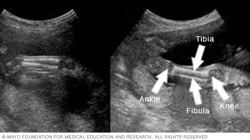

Below are images of the lower legs. The knee is on the right side of each image, and the ankle is on the left. You also can see the shinbone, called the tibia, and the small leg bone on the outside of the ankle, called the fibula.